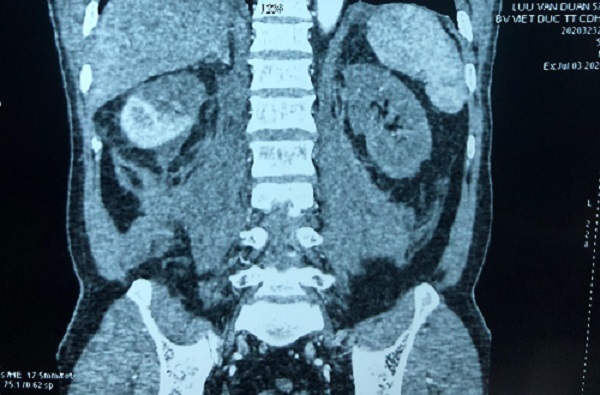

Mang thận ra rửa rồi ghép lại vào cơ thể bệnh nhân

Bệnh nhân đã có dấu hiệu suy thận nên các bác sĩ buộc phải tiến hành ghép thận tự thân để hai thận bổ sung chức năng cho nhau.